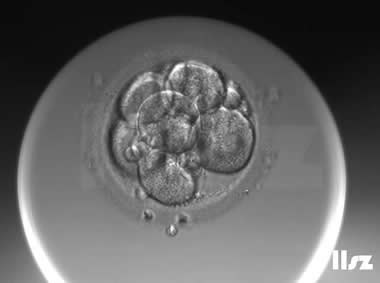

下面视频是胚胎在时差培养箱中培养至D3的整个过程,图片是D3(第68小时)的卵裂期胚胎图,本文D3胚胎评价是以D3时间点图片的形态学为依据,胚胎评级如下:

| Ⅱb级:该枚D3胚胎为7细胞,但碎片超过10%,因此评级为Ⅱb级。 | |